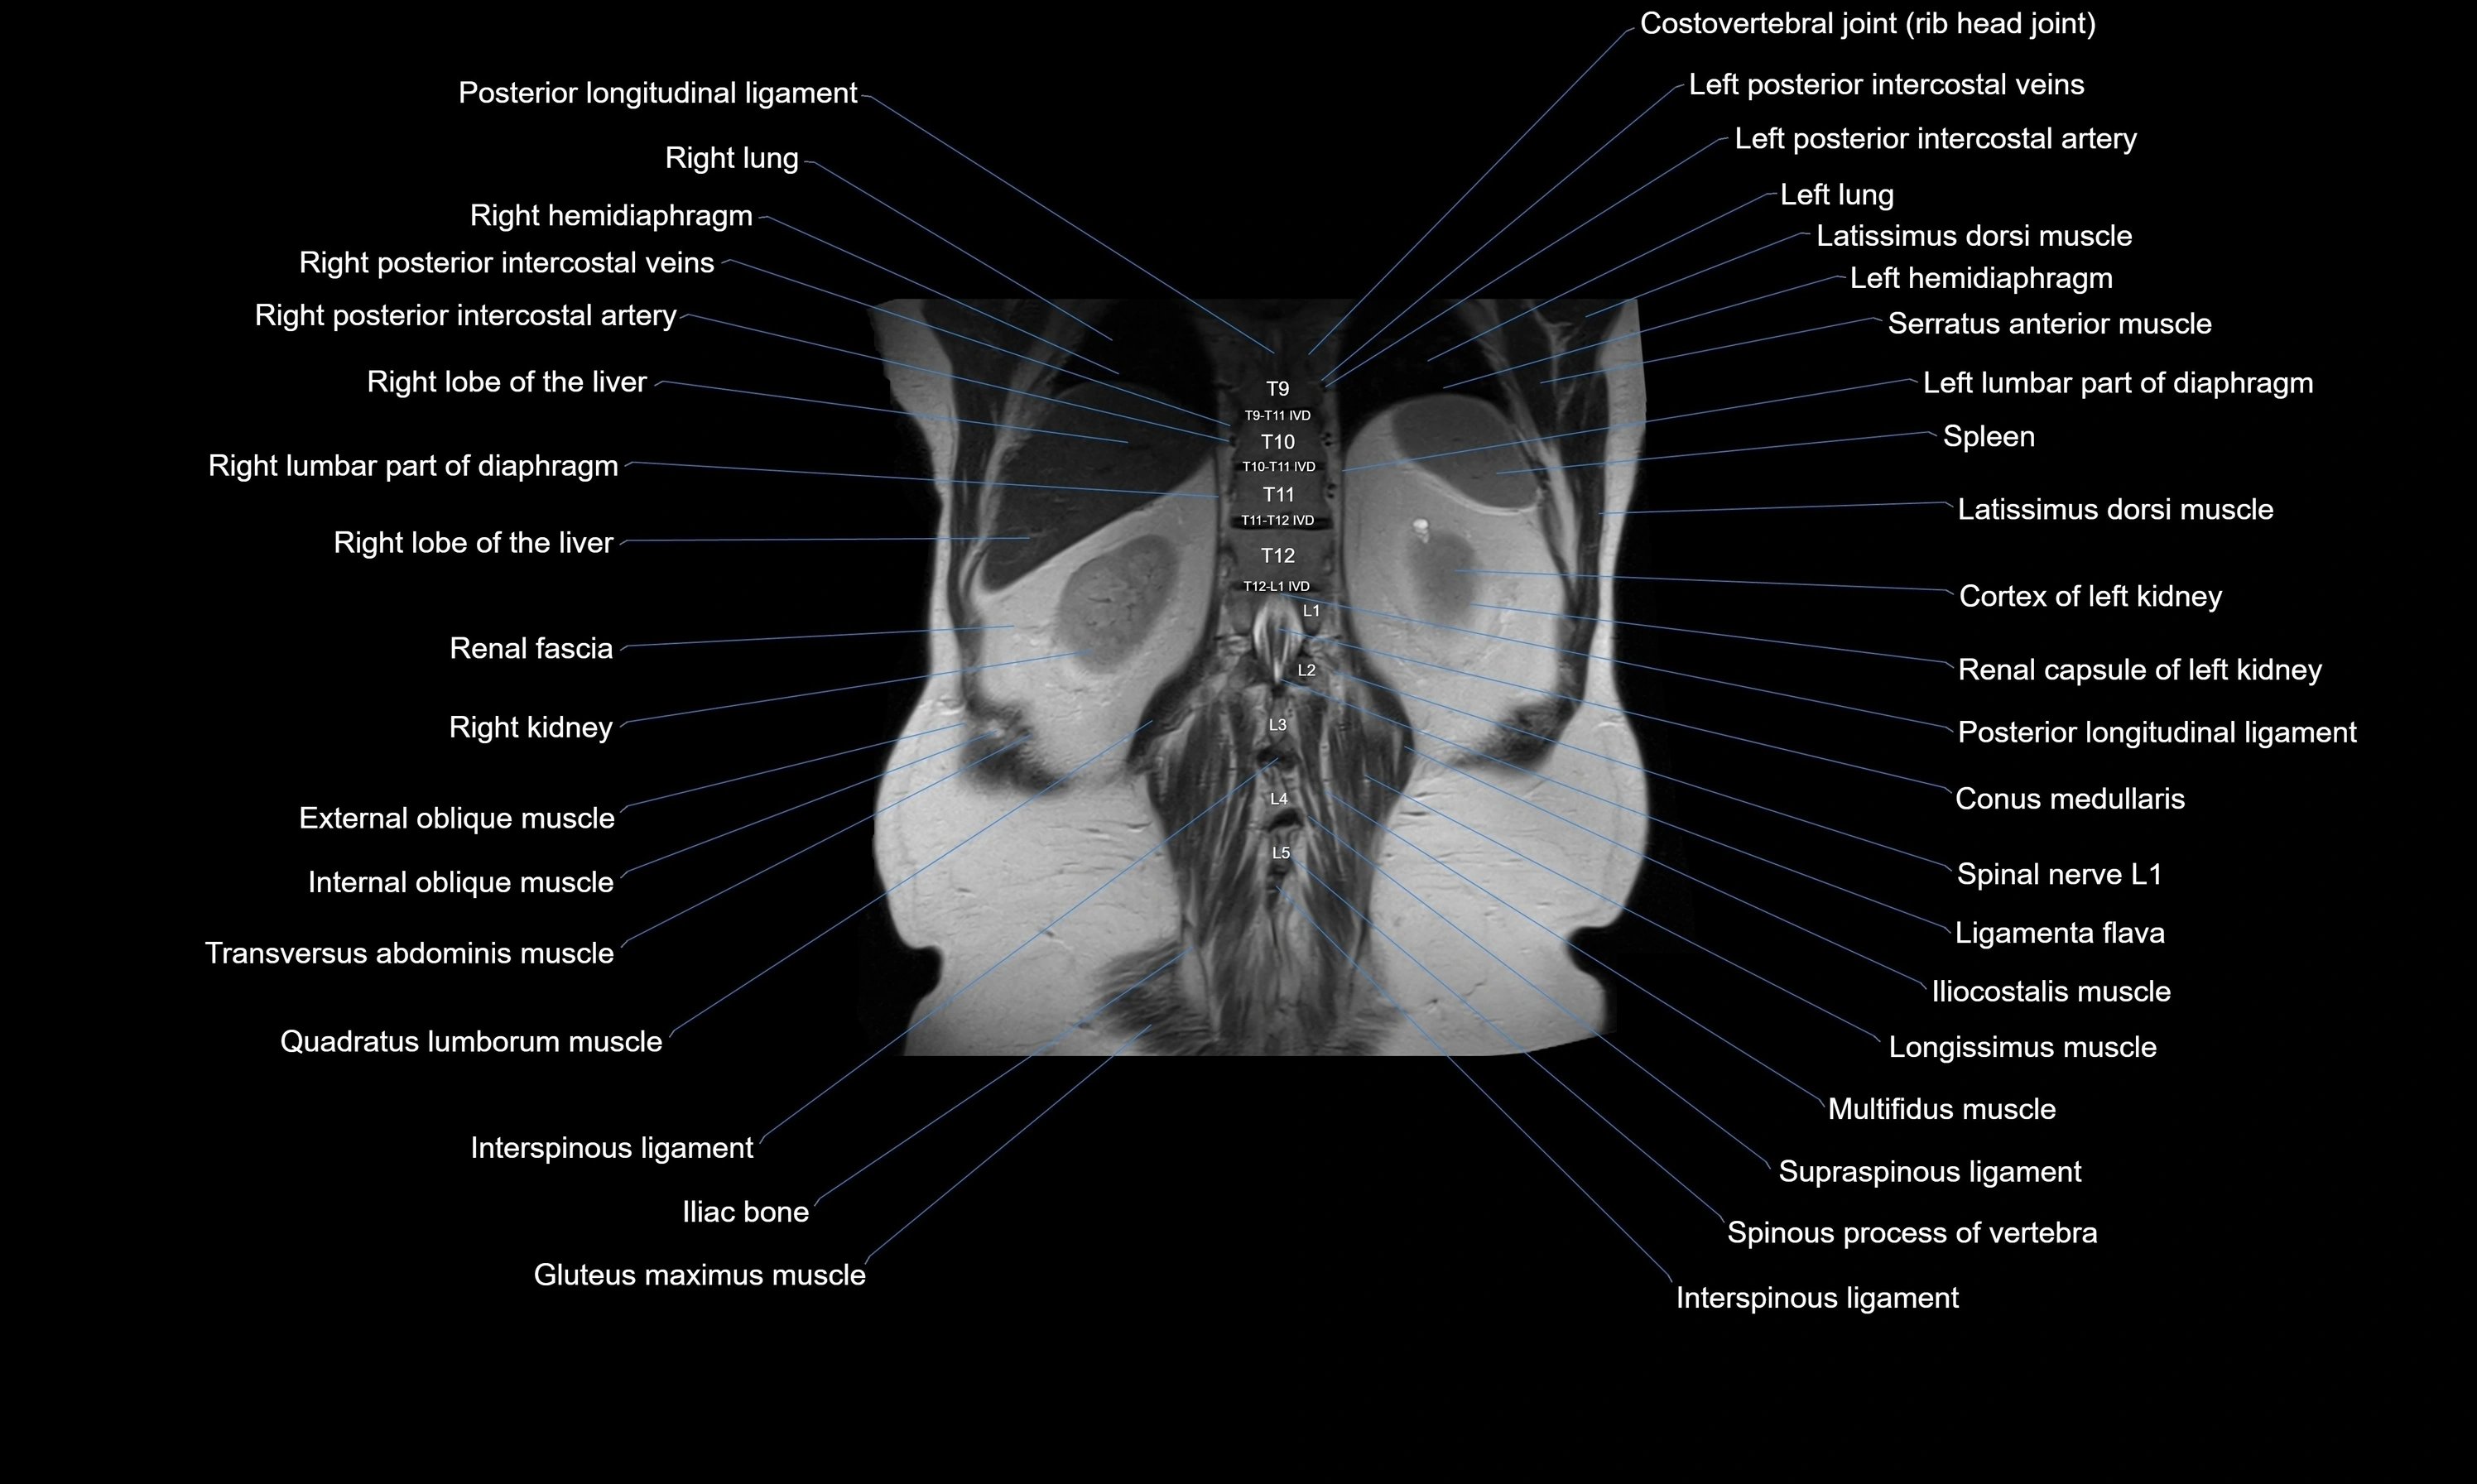

- Conus medullaris

- Gluteus maximus muscle

- Iliac crest

- Interspinous ligament

- Latissimus dorsi muscle

- Left hemidiaphragm

- Left lumbar part of diaphragm

- Ligamenta flava (Ligamentum flavum)

- Posterior longitudinal ligament

- Quadratus lumborum muscle

- Right kidney

- Right lumbar part of diaphragm

- Spinal nerve L1

- Spleen

- Supraspinous ligament